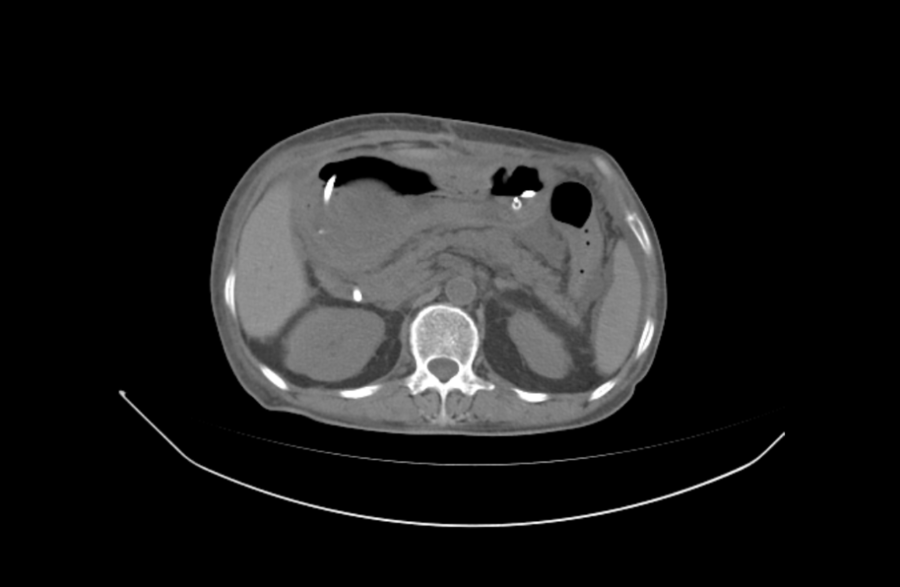

患者的求医之路充满坎坷。因肠梗阻在某医院行 “广泛肠黏膜松解术 + 胃空肠 Roux-en-Y 型吻合术” 后出现吻合口瘘,虽经相关治疗却未见好转,转至其他医院保守治疗亦无果。为求进一步治疗,患者来到济南南郊医院普外科,以 “手术后肠吻合口瘘” 收入院。

面对如此复杂且危急的病情,王兆太主任与李刚主任带领的普外科团队没有退缩。他们深知,每一次治疗决策都关乎患者的生死存亡,经普外科团队完善检查与深入了解病史,发现患者病情极为复杂。2023 年曾因腹膜后巨大肿瘤进行切除术,术后病理显示梭形细胞肿瘤,符合侵袭性纤维瘤复发 / 转移,术后复发肠梗阻。此外,患者还有 20 余年的 Ⅱ 型糖尿病、10 余年的高血压和冠心病病史,10 年前因甲状腺乳头状癌行甲状腺全部切除术。